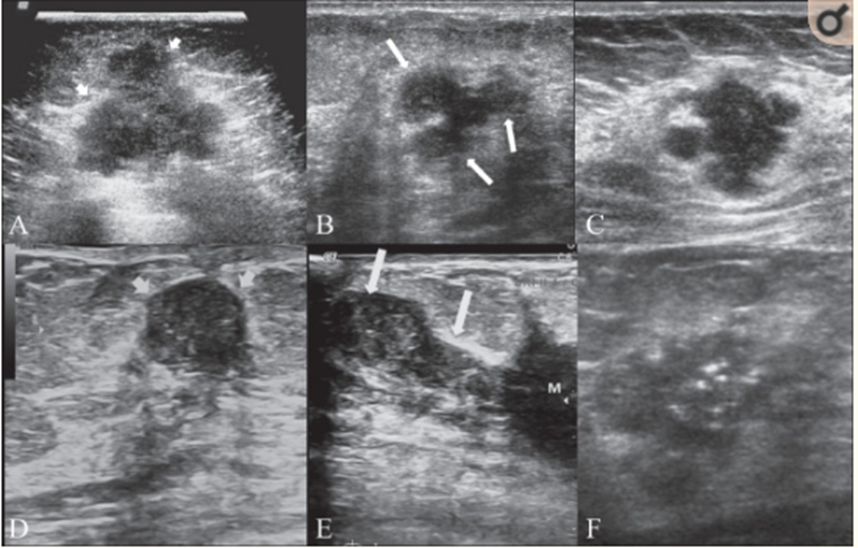

3.2 Siêu âm tuyến vú

Siêu âm vú là phương pháp chẩn đoán hình ảnh ung thư vú bằng cách xây dựng và tái tạo hình ảnh về cấu trúc bên trong tuyến vú và cơ thể. Siêu âm vú cũng hỗ trợ hướng dẫn mũi kim trong các thủ thuật xâm lấn như: Chọc hút nang, chọc hút sinh thiết, hướng dẫn kim sinh thiết có lõi,... Phương pháp này đang được áp dụng khá phổ biến vì chi phí thấp, dễ thực hiện, không đau và không gây hại cho bệnh nhân. Siêu âm chẩn đoán bệnh lý tuyến vú có độ chính xác cao, có thể chẩn đoán được những tổn thương nhỏ có đường kính dưới 5mm, có giá trị trong phát hiện ung thư vú sớm.

Với sự phát triển của khoa học kỹ thuật, các loại máy siêu âm ngày càng được tích hợp nhiều công nghệ hiện đại. Sự ra đời và phát triển của siêu âm đàn hồi mô càng làm tăng giá trị chẩn đoán của siêu âm trong chẩn đoán ung thư vú.

Khối ung thư vú trên siêu âm